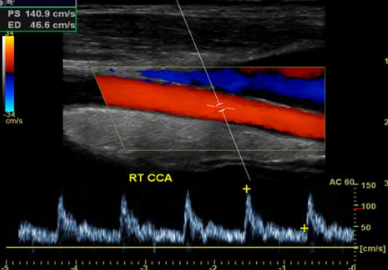

Our medical ultrasound imaging center uses advanced ultrasound technology for safe, non-invasive evaluation of organs, tissues, and blood flow.

Diagnostic ultrasounds require a medical order and include a variety of options such as abdominal, pelvic, thyroid, vascular, musculoskeletal, and obstetric ultrasounds. Whether your physician needs to assess internal structures, monitor blood circulation, or evaluate pregnancy health, our experienced Parker sonographers deliver clear results and compassionate care in a comfortable, welcoming environment.